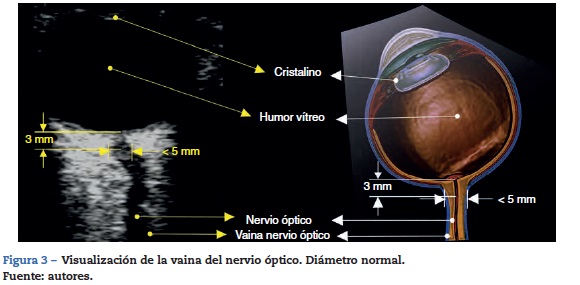

Se debe contar con un transductor lineal de alta frecuencia (7-10 mhz)22. El ecógrafo se configura para permitir visualizar estructuras hasta 5-6 cm de profundidad. El transductor se ubica sobre el párpado del ojo cerrado previa aplicación de abundante gel conductor.

El nervio óptico se identifica como la estructura hipoecoica de trayecto regular posterior al globo ocular. El estándar de medición requiere trazar una línea vertical que se inicia en la unión del nervio óptico con el globo ocular; esta línea es simplemente una referencia y debe medir 3 mm. Una vez localizados estos 3 mm se traza una línea horizontal de borde a borde del nervio óptico; esta segunda línea es la que mide el valor en milímetros del nervio óptico (figs. 3 y 4)32,33.

Para la mayoría de los autores revisados 5 mm es el punto de corte para que el estudio se considere positivo para hipertensión endocraneana; otros autores proponen valores diferentes (tabla 1).